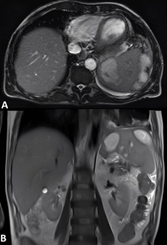

On the sixth day of hospitalization, a follow-up abdominal MRI showed confluence of some collections in the upper pole, measuring 6 and 8 cm in length, with no evidence of perisplenic abscess formation (Figure 3A, 3B).

Figure

3:

Abdominal MRI